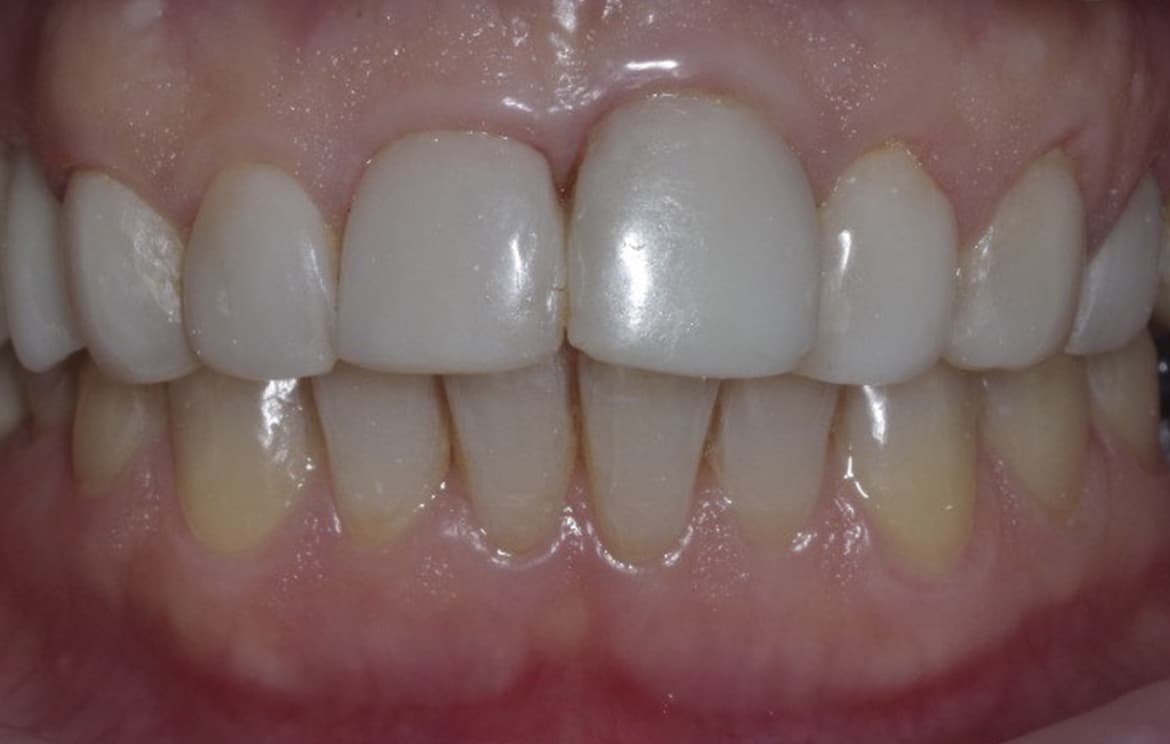

Наши работы